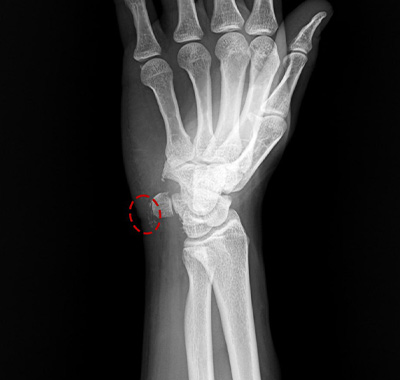

시술 당일 엑스레이를 통해 주사기로

흡입, 제거된 석회를 확인할 수 있습니다.

석회분쇄흡입술 전/후

석회성건염은 칼슘 퇴적물이 관절의 힘줄에 침착되며 염증과 통증을 유발하는 질환입니다.

석회성건염은 어깨, 팔꿈치, 고관절, 무릎, 손목. 발목 등 다양한 관절에 발생합니다.